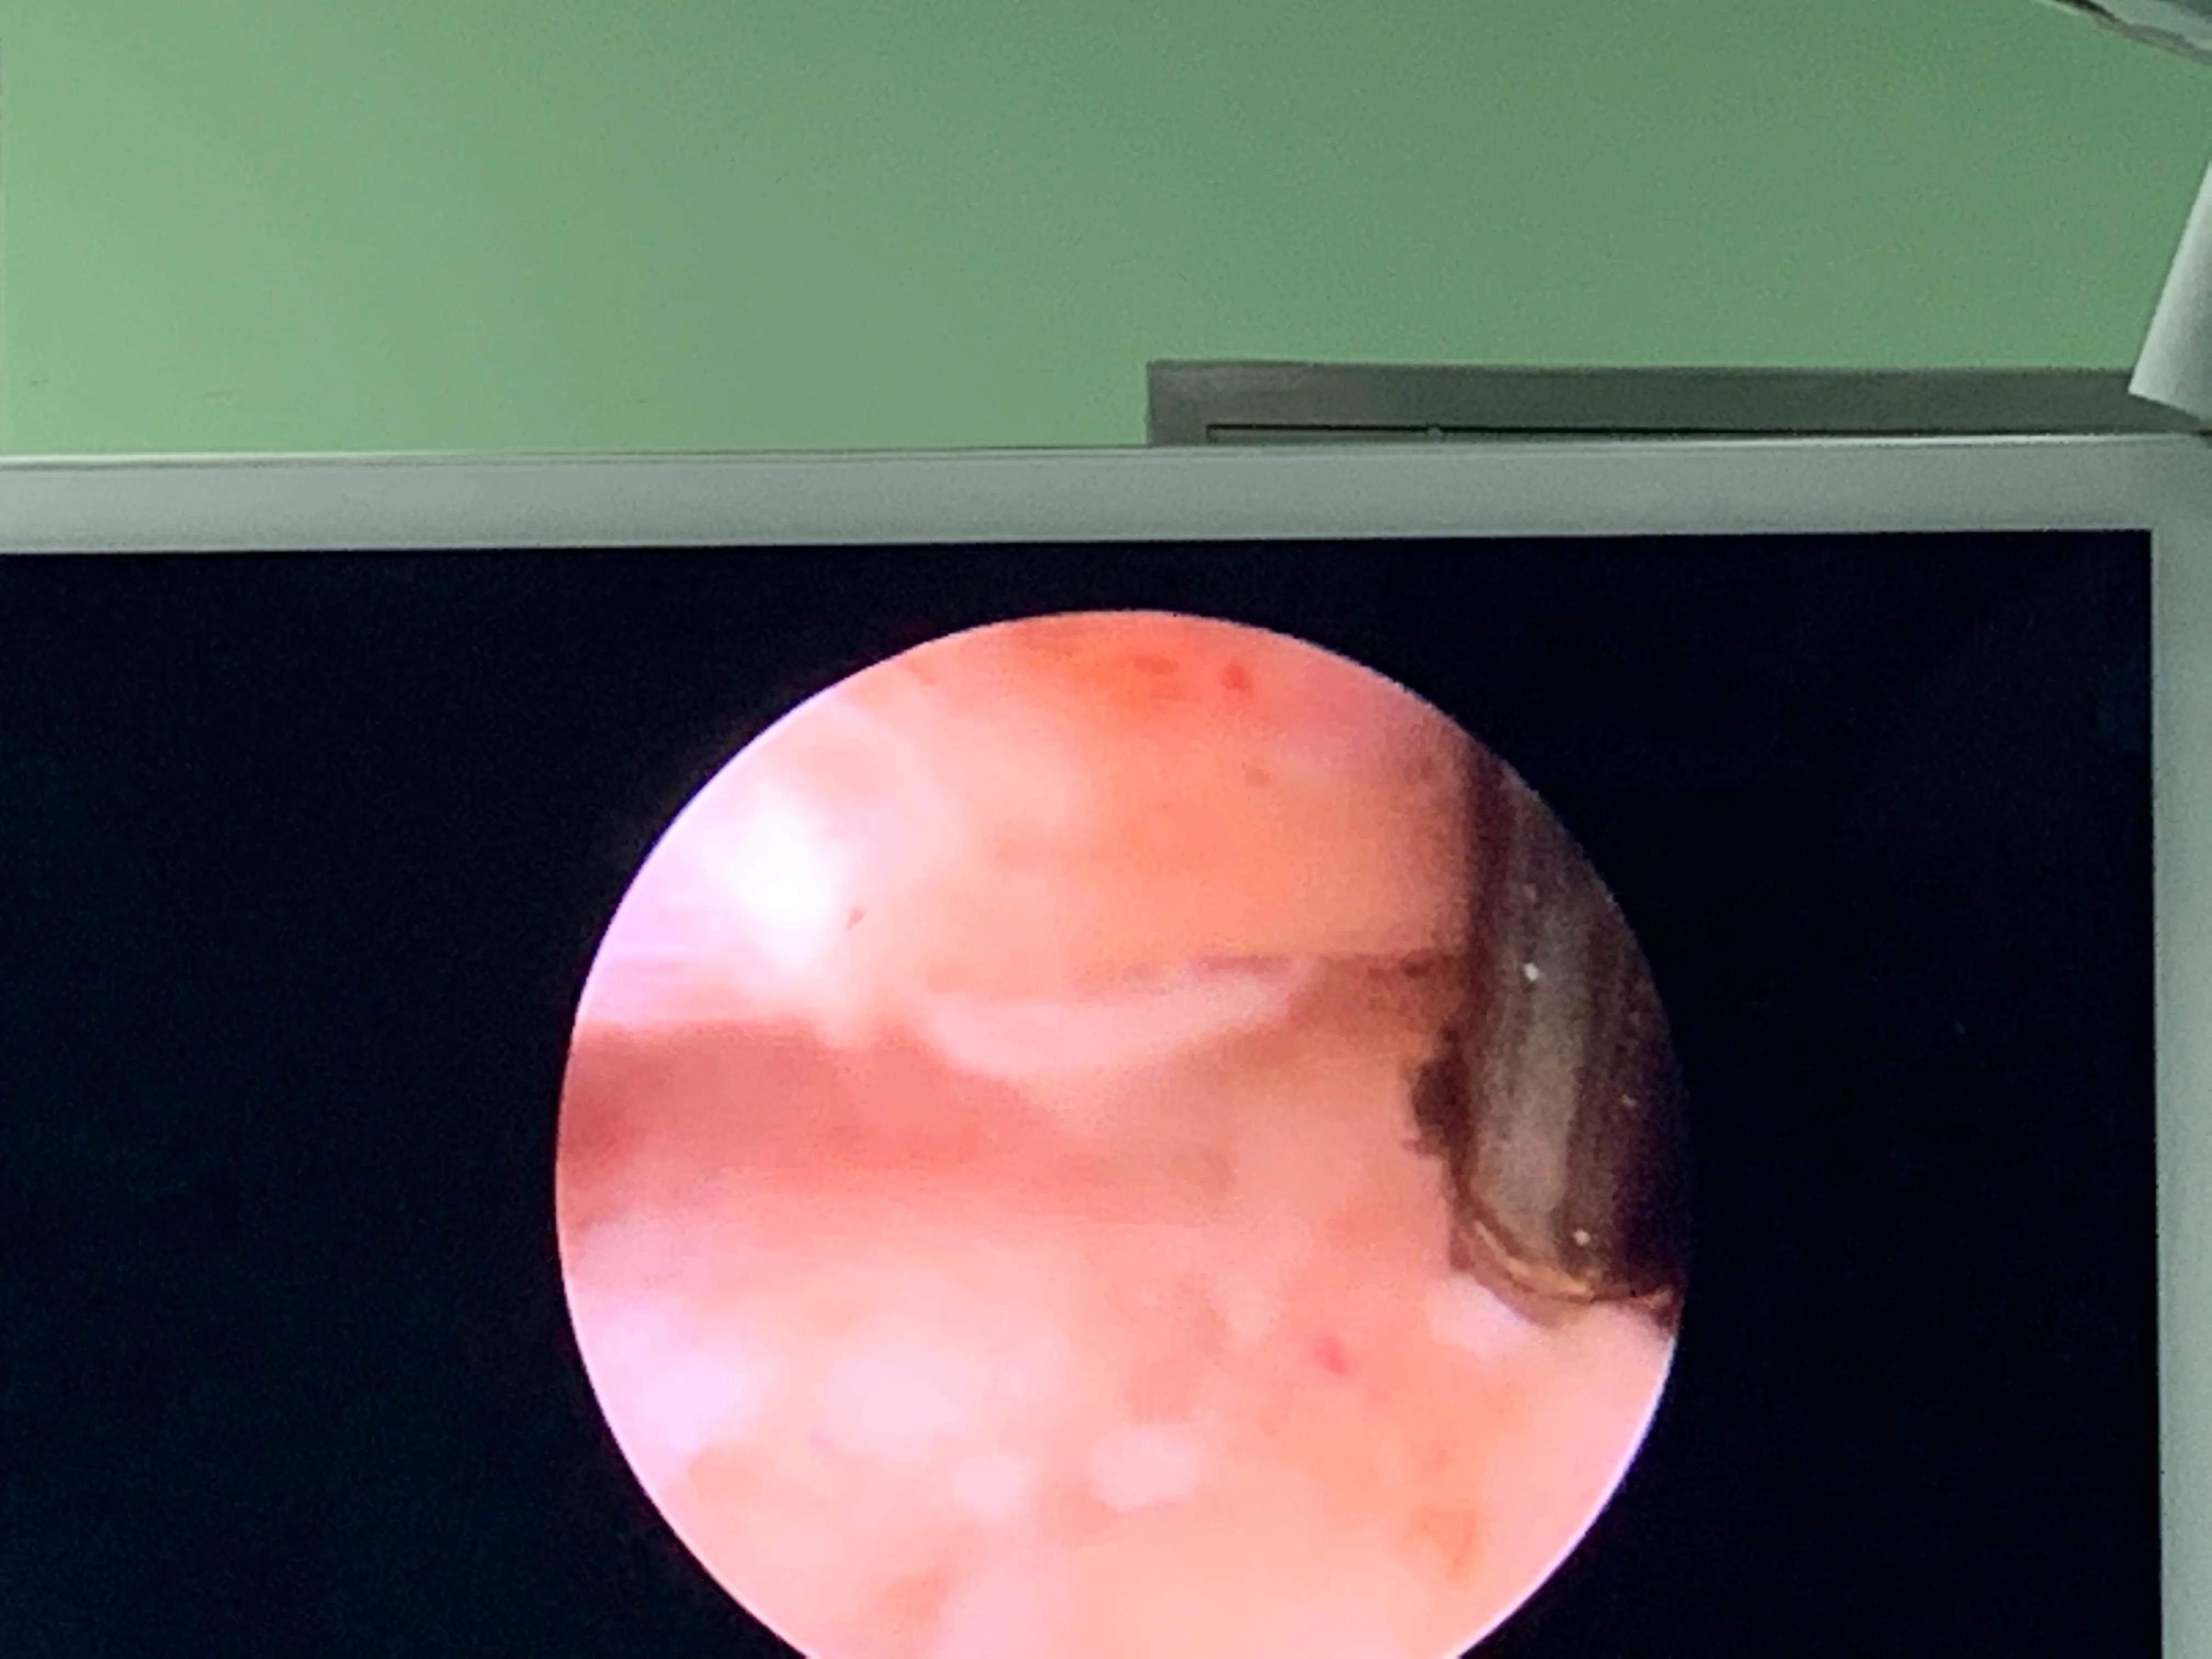

打开纤维环,去掉髓核

去除部分黄韧带

彻底松解神经根